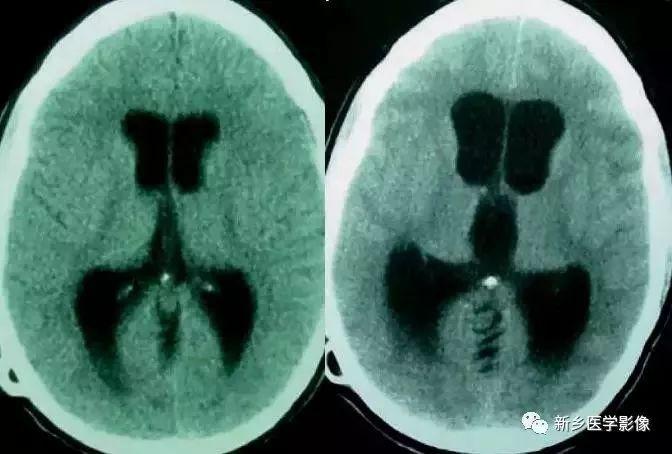

4.Dandy-Walker’s综合症

又称第四脑室中侧孔先天性闭锁。在胚胎早期期,第四脑室正中孔及侧孔闭寒,导致四脑室呈囊性扩张,并伴有小脑蚓部及半球发育不良,扩张之四脑室向后发展,并与枕大池相连,使后颅窝扩大,小脑幕抬高。本病出现脑积水通常见于婴儿期,或者出生后即存在,但到成人期才发病。